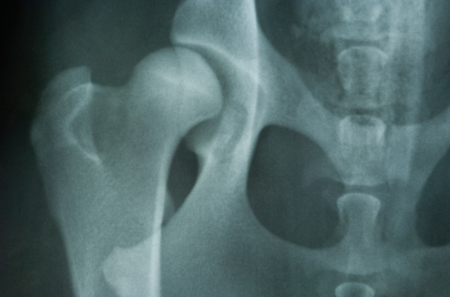

Verantwoorde fokkers vinden gezondheid en sociaal gedrag van de honden en hun nakomelingen belangrijker dan een mooi uiterlijk. Om gezonde honden te kunnen fokken, is het belangrijk dat de ouderdieren ook gezond zijn. Daarom laten verantwoorde fokkers hun honden onderzoeken op aandoeningen die binnen het ras voorkomen. Omdat ook de Raad van Beheer de gezondheid van de honden van groot belang vindt, houden wij de administratie bij van een aantal van deze onderzoeken. Op dit moment zijn dat de gezondheidsonderzoeken voor heupdysplasie (HD), elleboogdysplasie (ED), cochleaire doofheid (CD), DNA-koperstapeling, oogaandoeningen (ECVO) en patella luxatie. Dit zijn allemaal (deels) erfelijke aandoeningen die de ouderdieren aan hun pups zouden kunnen doorgeven.